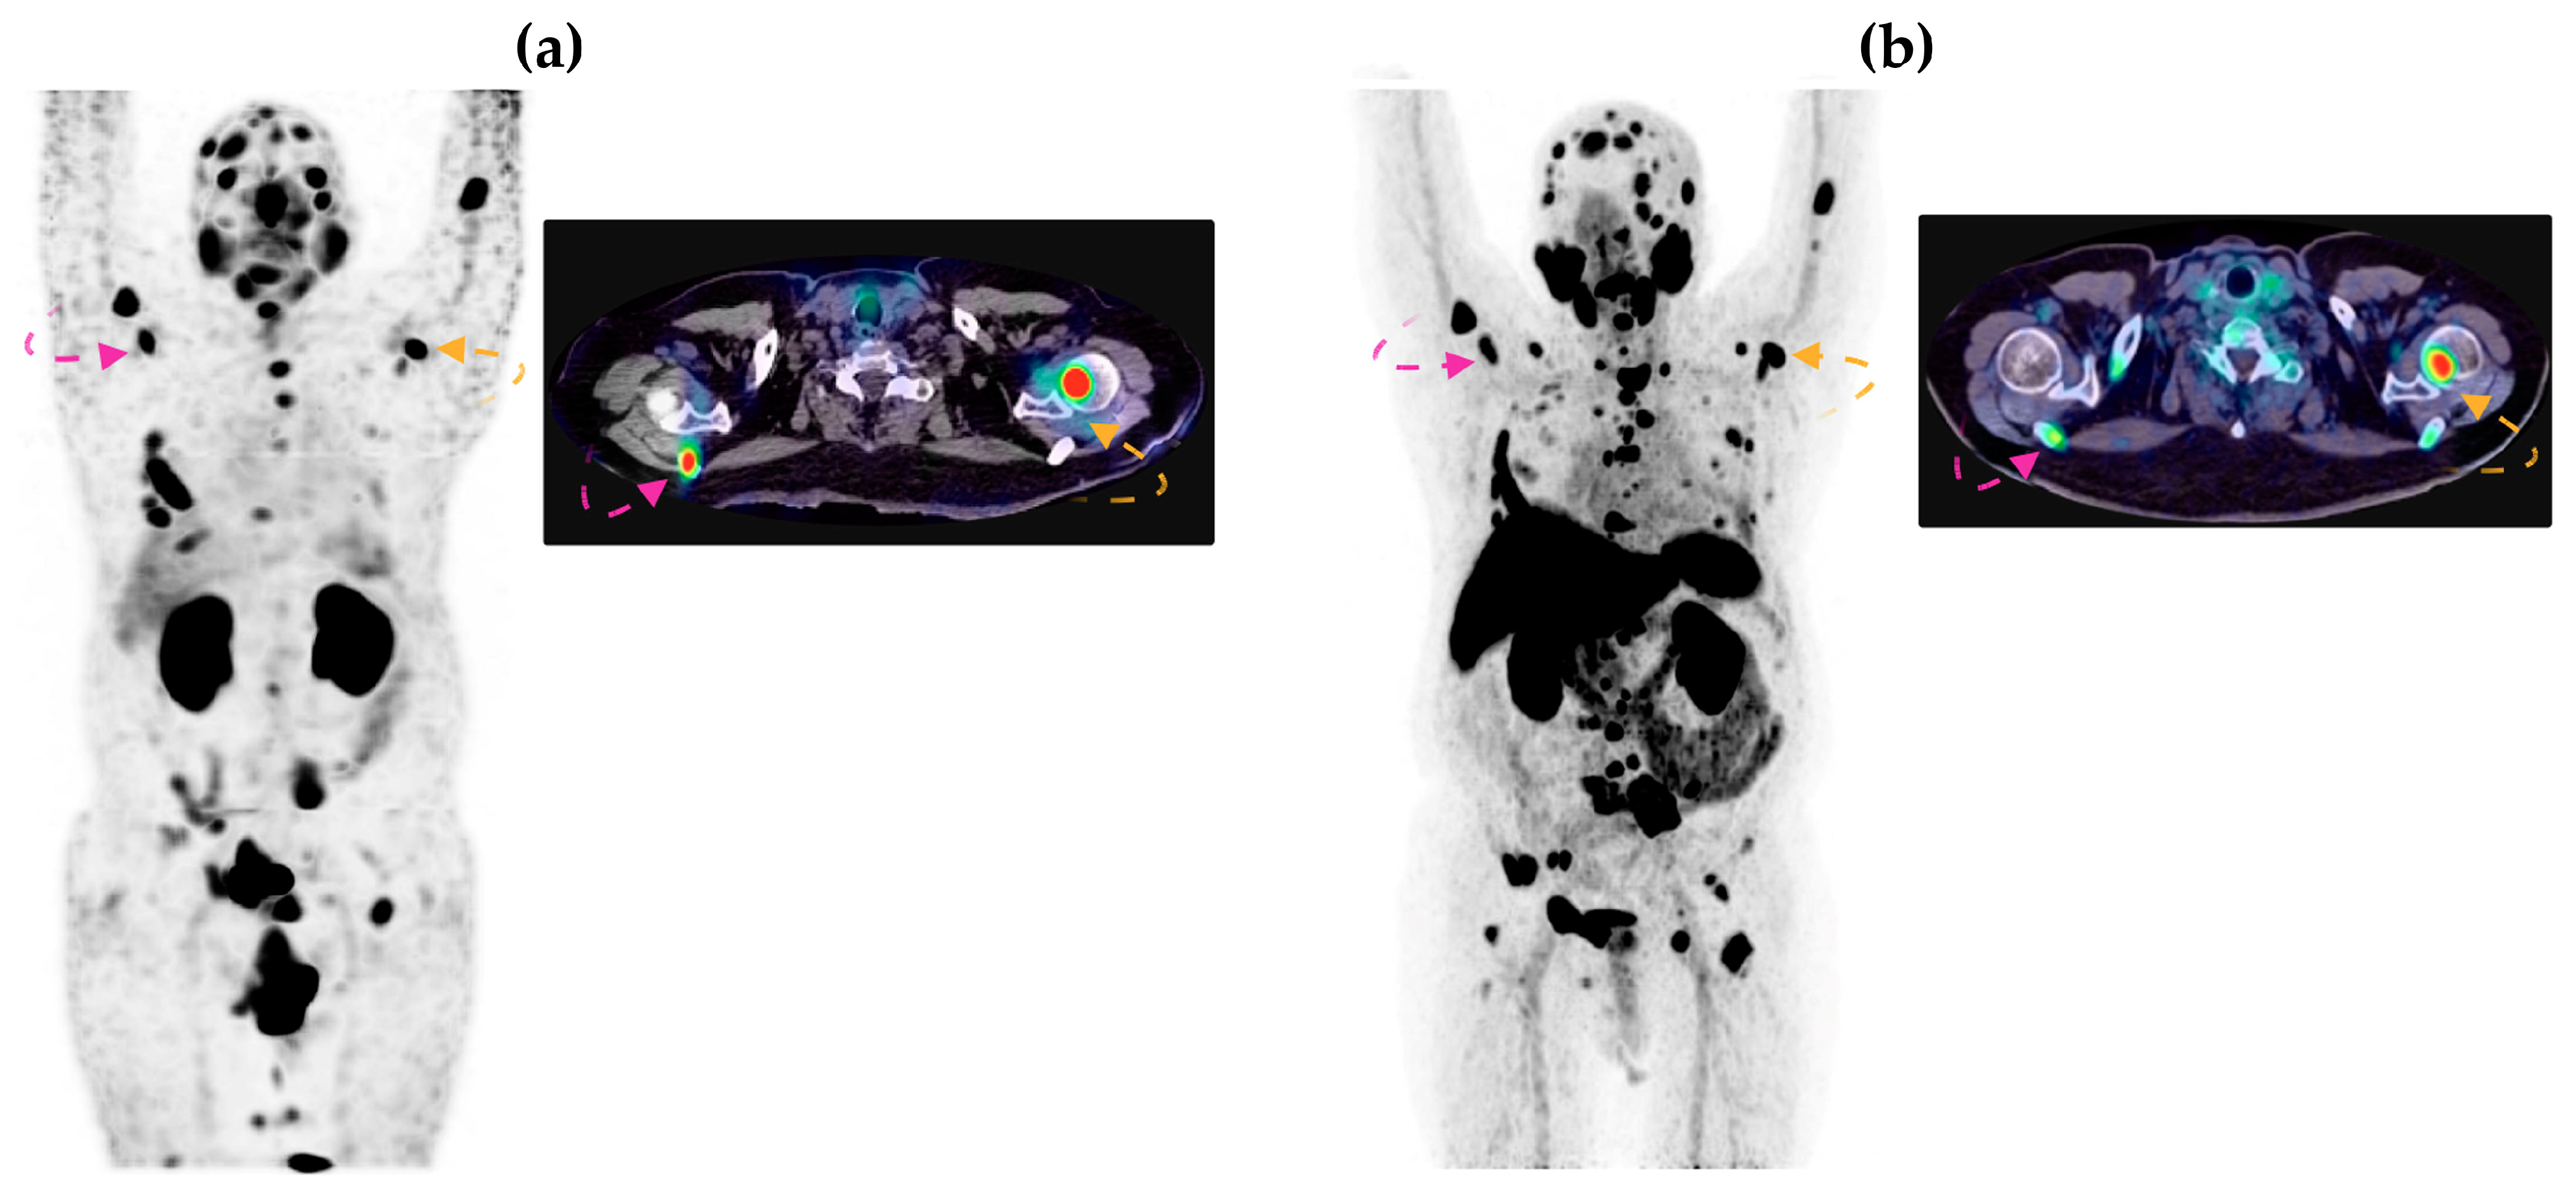

3.2.2. Imaging in Patients